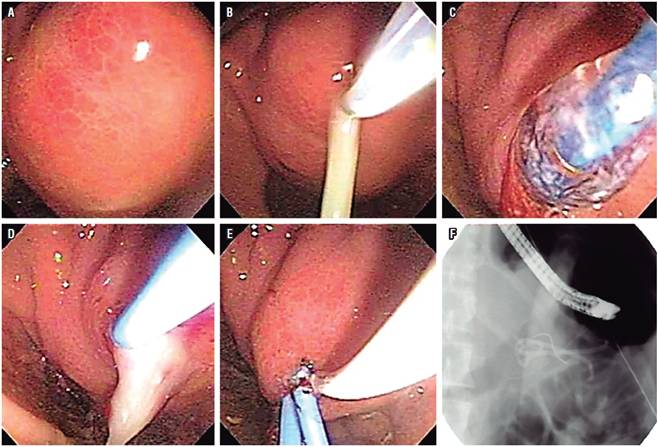

Terapia endoscópica para pp

Los PP son colecciones de jugo pancreático encapsulado, con una pared inflamatoria bien definida, que se desarrollan en el 20 %-40 % de los pacientes con PC. A diferencia de los PP de origen agudo, los de la PC raramente remiten espontáneamente. La intervención está indicada cuando los síntomas abdominales persisten (p. ej. dolor abdominal, náuseas, vómitos, saciedad precoz y pérdida de peso), obstrucción de la salida gástrica o biliar, o infección. Algunos tratamientos se han propuesto para colecciones asintomáticas persistentes que son grandes o que tienen una pared gruesa (reconociendo que ser asintomático no es común para quistes >6 cm) y aquellos que pueden estar asociados con fístula, cambios del ducto pancreático principal o con cálculos del ducto pancreático. El drenaje endoscópico de los pseudoquistes se puede realizar mediante abordajes transmurales y transpapilares 24.

Es importante evaluar la anatomía ductal anormal, incluidas las fugas ductales y si existe o no comunicación con el pseudoquiste, con una CPRM o CPRE previa al tratamiento. Un aumento en el tamaño del pseudoquiste en las imágenes sugiere comunicación ductal con el pseudoquiste. La presencia de obstrucción ductal debe manejarse antes de la terapia endoscópica para que la terapia de los pseudoquistes logre una mayor tasa de éxito y de este modo evitar la recurrencia. De forma similar, los pseudoaneurismas arteriales, si se detectan, deben embolizarse antes de realizar la terapia endoscópica porque la mortalidad asociada con hemorragia por pseudoaneurismas cercanos a los pseudoquistes es alta 25.

El drenaje transpapilar durante la CPRE es más útil para pseudoquistes pequeños, solitarios y comunicantes situados en relación con la cabeza y el cuerpo del páncreas. Este tipo de drenaje también se ha mostrado factible y útil en PP grandes y múltiples, sin mostrar unos resultados mejores o inferiores al drenaje transmural 26.

El drenaje transmural se puede realizar creando una comunicación entre el pseudoquiste y el estómago (cistogastrostomía) o el duodeno (cistoduodenostomía). Después de la punción, se deben colocar al menos 2 stents de plástico con doble cola de cerdo a través de la punción para mantener abierta la abertura entre el pseudoquiste y el estómago/duodeno. El stent no debe retirarse antes de 2 meses de la inserción y una imagen de corte transversal debe realizarse obligatoriamente para evaluar la resolución del quiste antes de la remoción del stent27.

Si hay evidencia de imágenes de un CPP seccionado, el stent debe mantenerse in situ indefinidamente para lograr los mejores resultados. Un intento por pasar con el stent la ruptura del conducto, si es posible, también se asocia con un buen éxito a largo plazo 28.

Antes del uso de USE en el drenaje del pseudoquiste, la presencia de una compresión en la pared gástrica o duodenal era esencial, y a través de ella se realizaba la punción/drenaje. Bajo guía ecoendoscópica lineal, el drenaje se puede realizar incluso para pseudoquistes no abultados que se encuentran incluso más allá de la luz gástrica o duodenal con resultados superiores 29. El USE también puede ayudar a delimitar un área avascular para la punción, lo que es de ayuda adicional en pacientes con colaterales vasculares extensas secundarias a hipertensión portal. El USE ofrece una ayuda adicional para distinguir los pseudoquistes de las neoplasias quísticas 30.

Se ha encontrado que tanto el drenaje transpapilar como el transmural de los PP tienen un éxito similar a largo plazo, mientras que el primero tiene una morbilidad menor (1,8 % frente a 15,4 %; p <0,008). Aunque el drenaje transmural del pseudoquiste puede realizarse mediante drenaje convencional y guiado por USE, la tasa de éxito es mayor con el drenaje guiado por USE porque no requiere la presencia de una compresión intraluminal. Los resultados son más favorables para el pseudoquiste localizado en la cabeza del páncreas 11 (Figura 4).